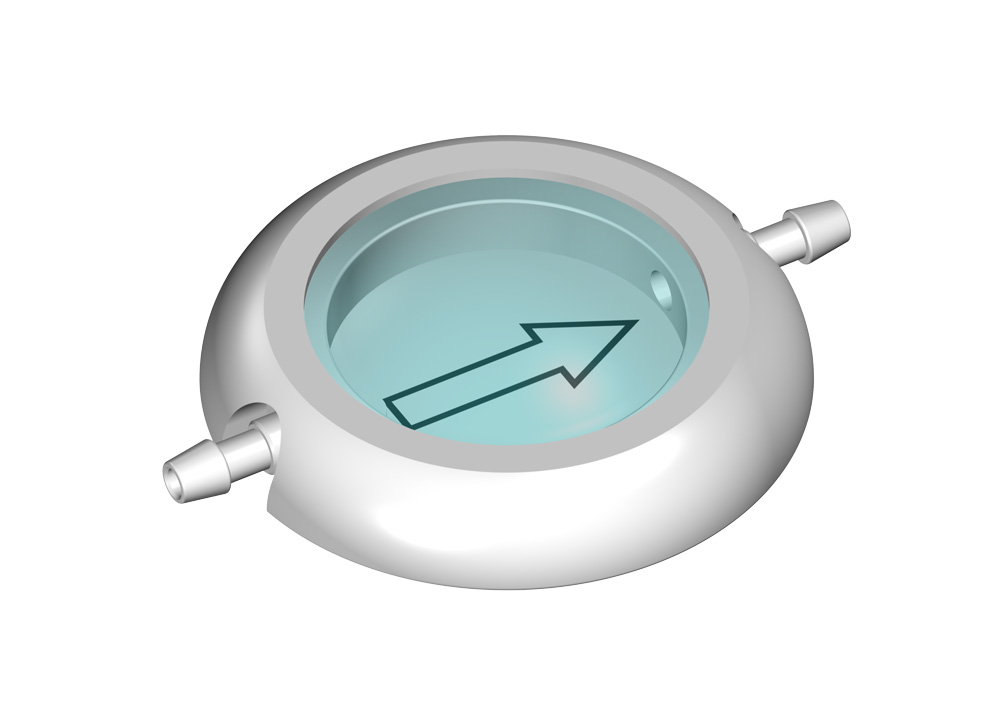

MIETHKE Vorkammern

Ein solches CONTROL RESERVOIR bzw. eine Vorkammer ermöglicht die Messung des intraventrikulären Drucks, die Injizierung von Medikamenten und ggf. eine Ventilkontrolle. Eine Entnahme von Liqour und Zugabe von Medikamenten kann durch die Punktion der Silikonmembran mit einer Kanüle erfolgen. Der solide Titanboden verhindert dabei das Durchstechen mit einer Kanüle.

Alle MIETHKE CONTROL RESERVOIRE und Vorkammern sind gut erkennbar im Röntgenbild und bedingt MR sicher, d.h. Kernspinresonanzuntersuchungen (MR) oder computertomographische Untersuchungen (CT) können ohne Beeinträchtigung des Patienten durchgeführt werden.

Die Reservoire sind für Katheter mit einem Innendurchmesser von ca. 1,2 mm und einem Außendurchmesser von ca. 2,5 mm ausgelegt (außer LP-Vorkammer).